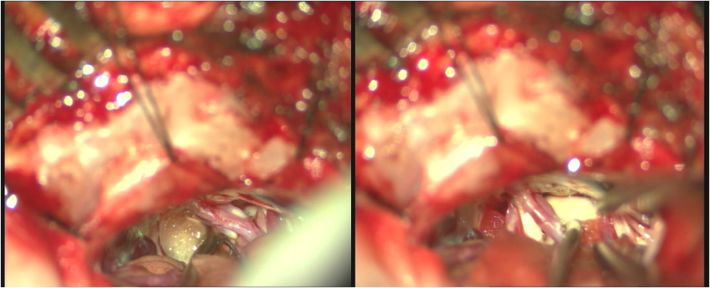

术前影像

![]()

术前阅片考虑责任血管为右侧迂曲椎动脉,同时压迫面神经及三叉神经。